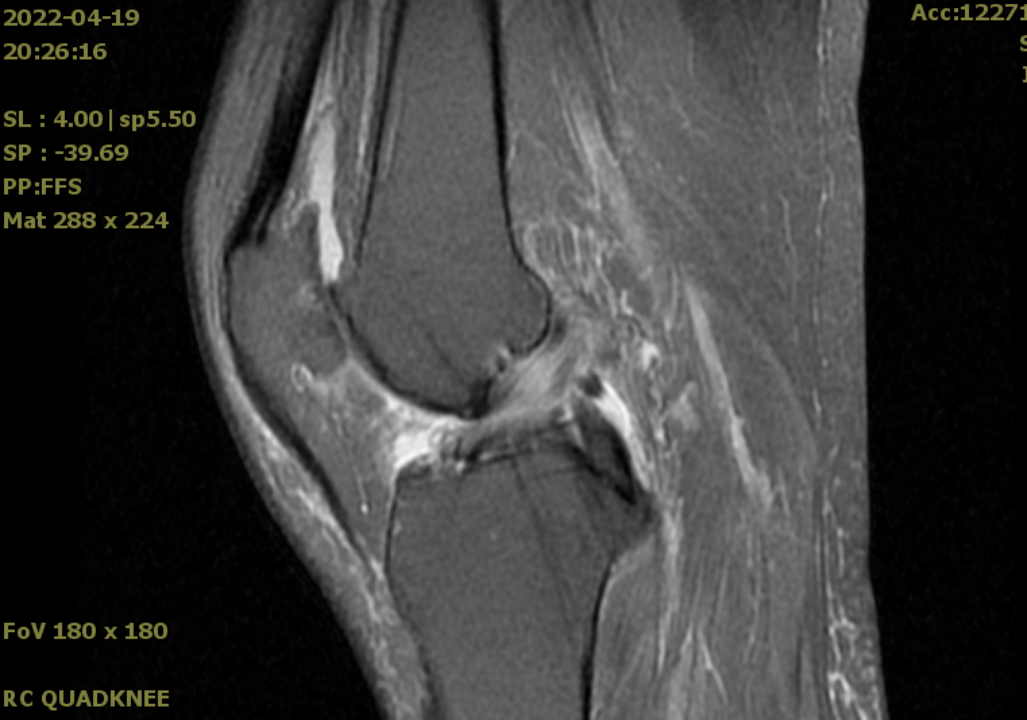

1、前内侧骨关节炎(AMOA),股骨内侧髁或胫骨内侧平台骨坏死

2、前交叉韧带ACL 完好、内侧副韧带MCL 功能完好

3、外侧软骨正常或轻微退

4、内翻畸形 <15°,屈膝畸形 <15°,膝关节可主动屈曲 ≥90°

1、ACL、MCL 缺失或严重损伤

2、关节内畸形不能被手动矫正

3、屈膝畸形 >15°,麻醉下膝关节被动屈曲 <100°

4、外侧间室软骨缺损